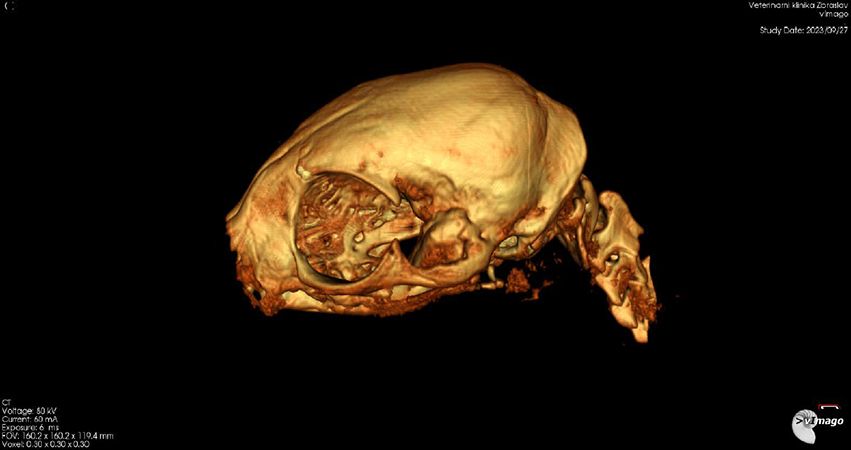

Leo absolvuje nové CT vyšetření. Je zřejmé, že oproti původní diagnóze (špatně zhojené poškození měkkých tkání), je z nových snímků jasně patrné, že Leo má špatně zhojenou zlomeninu spojení spodní čelisti a podočnicového oblouku na levé straně, což je důvod, proč se mu pusinka opět zavřela. Je nutná operace. Po krátké konzultaci v Nuslích Linda domlouvá, aby Lea odoperovali akutně na Zbraslavi. Dostává zprávu, 3D model i CT snímky do mailu.